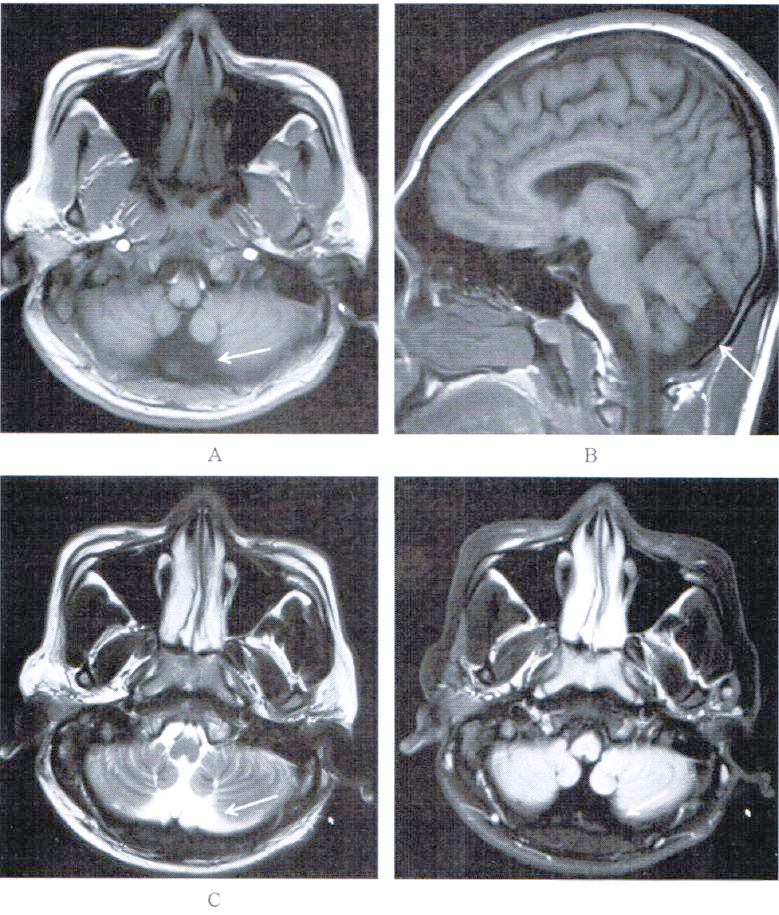

大枕大池及其鉴别诊断详解

有人写大枕大池有人说是枕大池蛛网膜囊肿有依据吗今天我们就来讨论一